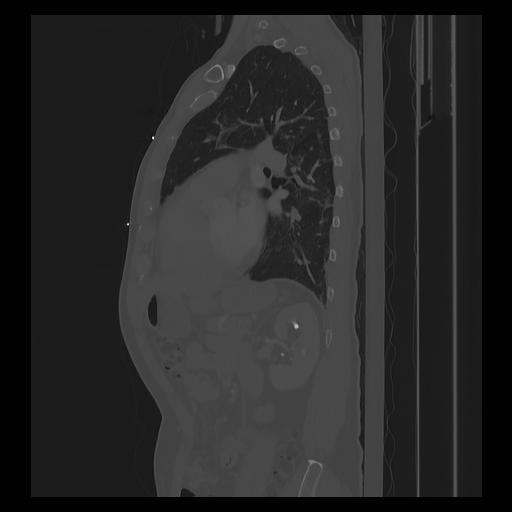

33 PULMON,CE,Sagittal,3.000,PULMON,Sagittal,